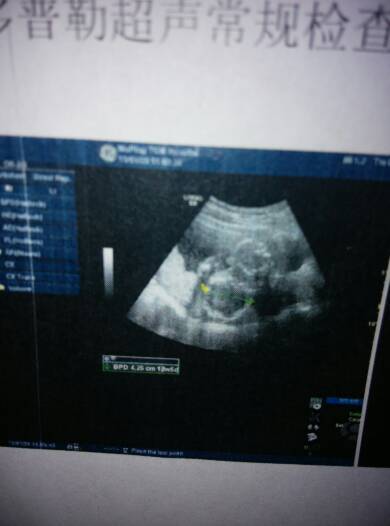

18周做的彩超,亲爱的宝妈们谁能帮我看看男孩女孩,双顶径4.2头围15.0腹围12.6股骨长2.7

18周做的彩超,亲爱的宝妈们谁能帮我看看男孩女孩,双顶径4.2头围15.0腹围12.6股骨长2.7,谢谢😜

你好,看超声检查的报告是不能判断胎儿的性别的,建议按时产检,在孕期的24周左右检查四维超声了解胎儿的情况吧。

你好,彩超报告只提供了宝宝的大小,而没有提供宝宝的性别,而且正规医院是不允许做性别鉴定的。